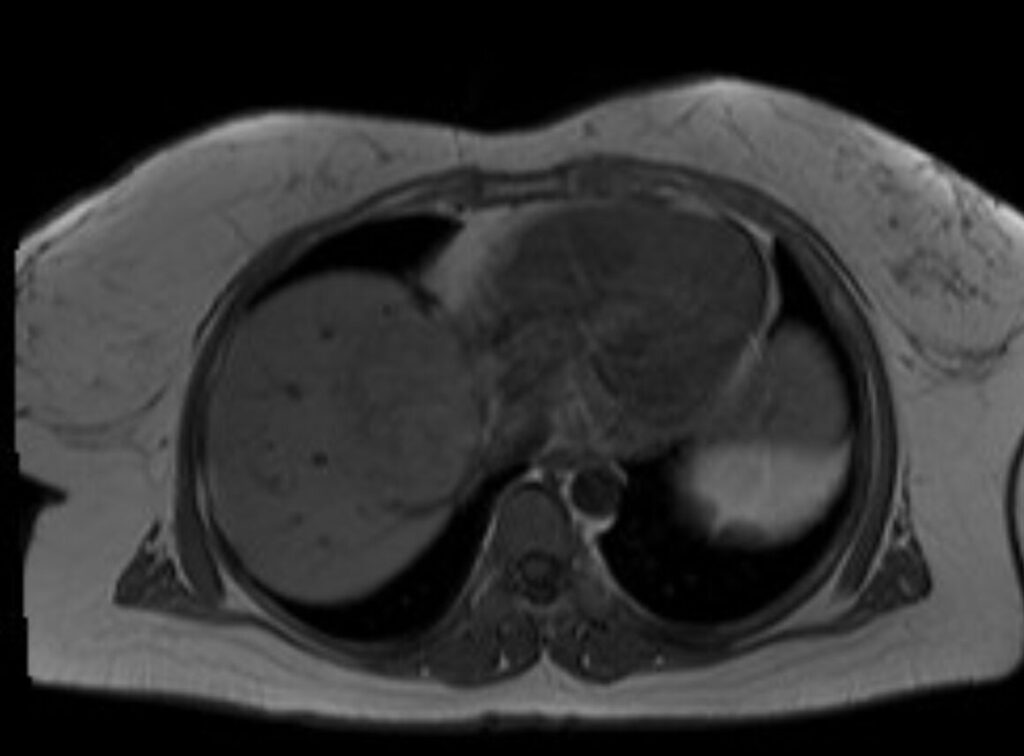

Aspetto RM

- Alterazione focale ben circoscritta, ipointensa in T1, iperintensa in T2 (isointensa al liquor), priva di enhancement post-contrastografico.

- Nelle sequenze colangiografiche non si riconosce una comunicazione con l’albero biliare.

- La cisti epatica a contenuto proteinaceo ha segnale iperintenso in T1.

- Nel caso di emorragia intracistica, il segnale sarà eterogeneo sia nelle sequenze T1 che T2, spesso con un livello fluido-fluido.